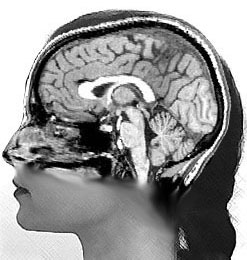

world's only university for the deaf), she began a Ph.D. program at the

University of Chicago, where she fell hard for Psycholinguistics. She first

worked in a gesture research lab, and later took up with a brain research lab,

where she conducted the experiments that would earn her a degree in 2004. By